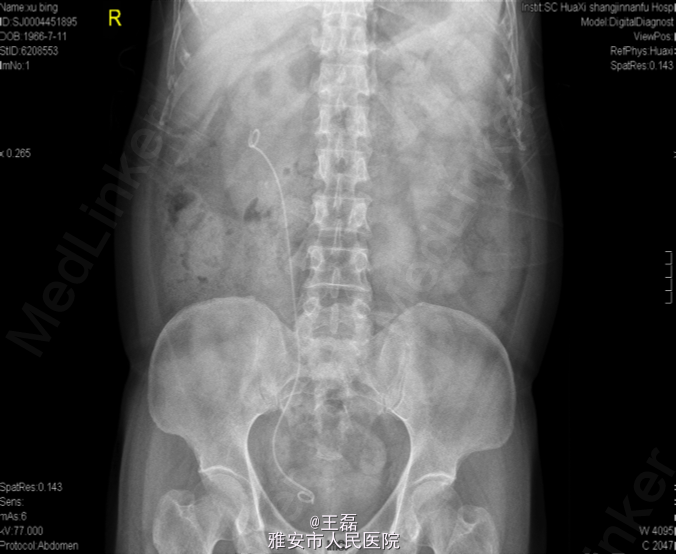

诊断为右肾下盏结石; 手术:右侧输尿管软镜钬激光碎石取石术

术后结石清除干净,嘱患者倒立,多运动促排石。 术后结石成分分析:结石成分:一水草酸钙,二水草酸钙,碳酸磷灰石 影响结石形成的因素很多,年龄、性别、种族、遗传、环境因素、饮食习惯和职业与结石的形成相关。一般如果结石成分像这类患者是钙相关的话,可以建议患者多饮水(>2500ml),每天适当喝鲜榨橘汁橙汁,低盐低蛋白饮食。